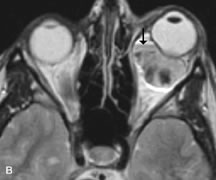

MRI is particularly helpful in the detection and characterization of subperiosteal hematomas of the orbit (Fig. 19). They are most commonly seen in the subperiosteal space of the superior orbit as well-defined masses following a traumatic injury. The signal intensity varies depending on the acute, subacute, or chronic nature of the hematoma, based on the stage of blood degradation. Fresh hemorrhages are hypointense on T1-weighted images and hyperintense on T2 images. Hematomas that are 1 to 7 days old are hypointense on both T1- and T2-weighted images. T1-weighted images of hematomas more than a week old are hyperintense due to the oxidation of deoxyhemoglobin to methemoglobin, whereas the T2 images remain hypointense.63

Fig. 19. A. T1- and (B) T2-weighted MR scans demonstrate a large acute subperiosteal hematoma (H) that lies between the cortical bone of the orbital roof and the inferiorly displaced periorthira (double arrow). The extracopal fat (arrow) and levator muscle are displaced inferiorly.